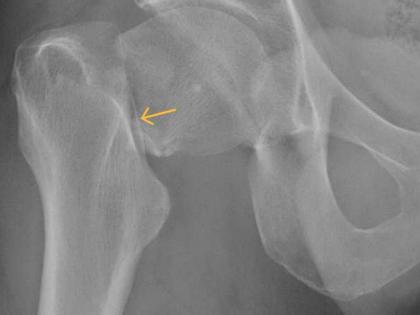

अलिकडे लोक पेनकिलर गोळयांचं अधिक सेवन करतात. त्यात साधारणपणे ट्रामडोलचं सेवन केलं. पण या गोळीचं सेवन अधिक केल्याने हिप फ्रॅक्चरचा धोका वाढू शकतो. नुकत्याच करण्यात आलेल्या एका रिसर्चमध्ये सहभाग घेतलेल्या तज्ज्ञांनी सांगितले की, ट्रामडोलचा वापर काळजीपूर्वक केला पाहिजे. कारण याचं फार जास्त सेवन कराल तर हिप फ्रॅक्टरचं कारण ठरू शकतं. खासकरून ५० पेक्षा अधिक वय असलेल्या लोकांमध्ये ही समस्या अधिक बघितली गेली आहे.

हिप फ्रॅक्टर आणि ट्रामाडोलमधील संबंध समजून घेण्यासाठी अभ्यासकांनी यूनायटेड किंगडममधील ५० वयापेक्षा लोकांचा रिसर्चमध्ये समावेश केला होता. या लोकांना कधीच हिप फ्रॅक्चर, कॅन्सरसारखी समस्या झाली नव्हती. या रिसर्चमध्ये १७ वर्षाच्या उपलब्ध डेटाबेसचा देखील वापर करण्यात आला. या रिसर्चमध्ये ५६.९ टक्के महिलांचा देखील समावेश होता.

या रिसर्चदरम्यान एक वर्ष फॉलोअपमध्ये १, ४६, ९५६ लोकांपैकी ५१८ लोकांमध्ये हिप फ्रॅक्चर आढळून आला. ज्यामुळे अन्य पेनकिलरच्या तुलनेत ट्राडामोलने हिप फ्रॅक्चरचा धोका अधिक होत असल्याचं सांगण्यात आलं.